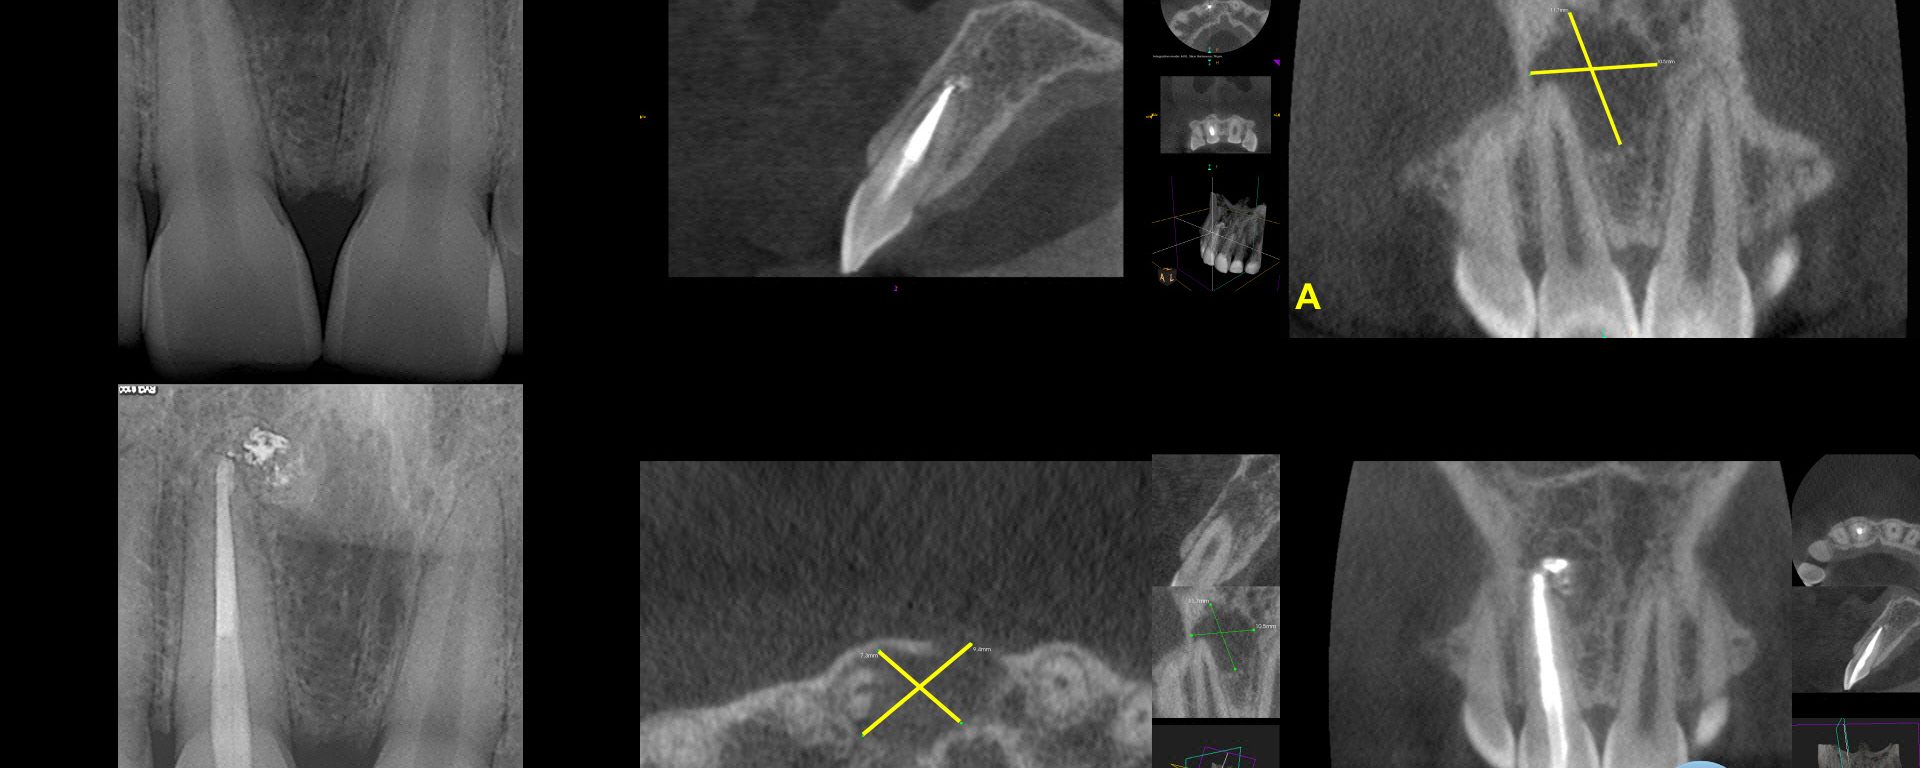

Resolved.